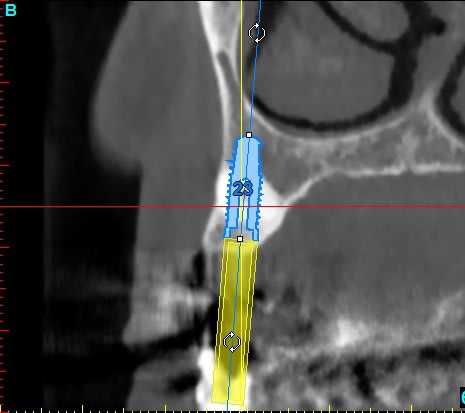

patiente de 80ans, canine incluse depuis donc pas mal de temps. ATCD de prothese amovible depuis 15ans. Je crains que sa canine soir hyper ankylosé et je me propose donc d'implanter au travers.

le problème c'est que le logiciel 3D ne réfléchit pas il donne juste de belles images

je n'ai jamais pensé que c'était la meilleur des solutions; néanmoins, si la canine est ankylosée (au bout de 65ans planquée dans l'os y'a des chances),son extraction va pas être sympa, risque de compromettre le bridge antérieur et donc de finir en all on 6 (dont le coût tissulaire, et financier et temps de traitement n'est pas le même).

C'est bien ma crainte mais j'ai plusieurs questions : les forets antogyr ne risquent-ils pas de déraper au contact de la racine de 13 ?

Y a-t-il bien une sidération nerveuse de 13 qui m'évite tout tt endo de 13 (impossible en laissant 13 en place d'ailleurs)?

tu as davarpannah qui a référencé des cas et ce n'est pas une si mauvaise idée. fais attention à ne pas chauffer, une dent ce n'est pas de l'os, à avoir des forets neufs bien coupants. a un age avancé une extraction de canine incluse ( obligatoirement délabrante) + reconstruction osseuse derriere+ implant c'est long , douloureux et .....chiant